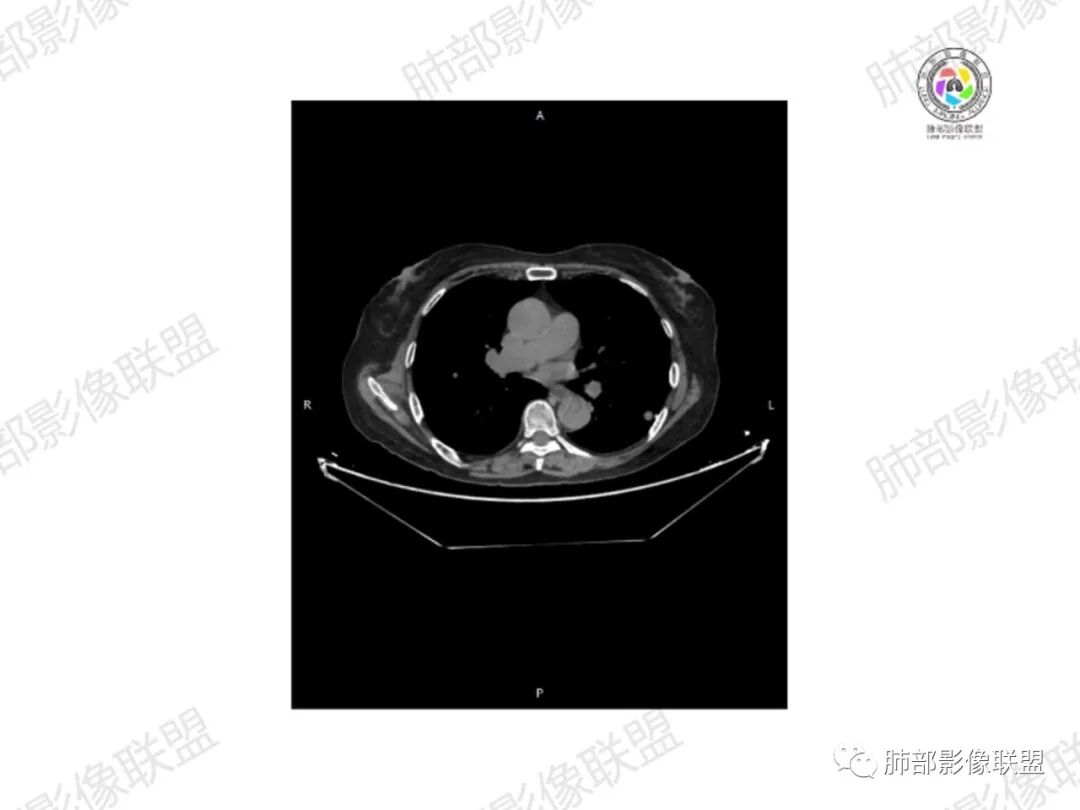

5.双肺多发类圆形结节影,边界清楚,随机分布,其间多见钙化密度影。

6.双肺门及纵隔未见肿大淋巴结。

3.双肺病灶符合转移瘤,伴有中央部分钙化者也以骨肉瘤转移较为多见。